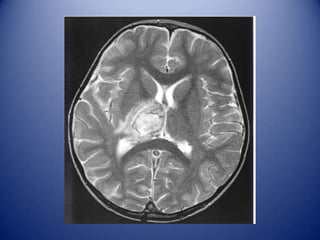

MRI white-matter lesions in NPSLE

↑ signal in Τ2 / FLAIR

• Localized in subcortical and periventricular

white matter and frontal-parietal lobe (70–80%)

• Prevalence 50–60% of all patients with NPSLE

…but 18–40% of non-NPSLE

…no correlation with a particular NP syndrome

• Cerebral atrophy, number and size of WML and cerebral infarcts

correlate with severity of cognitive dysfunction

In young SLE patients new MRI WMLs (especially if ≥5, ≥6-8mm, and

bilateral may suggest active NPSLE